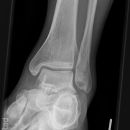

Totale Talusluxation

Talus Fraktur

Snowboard fracture Talus